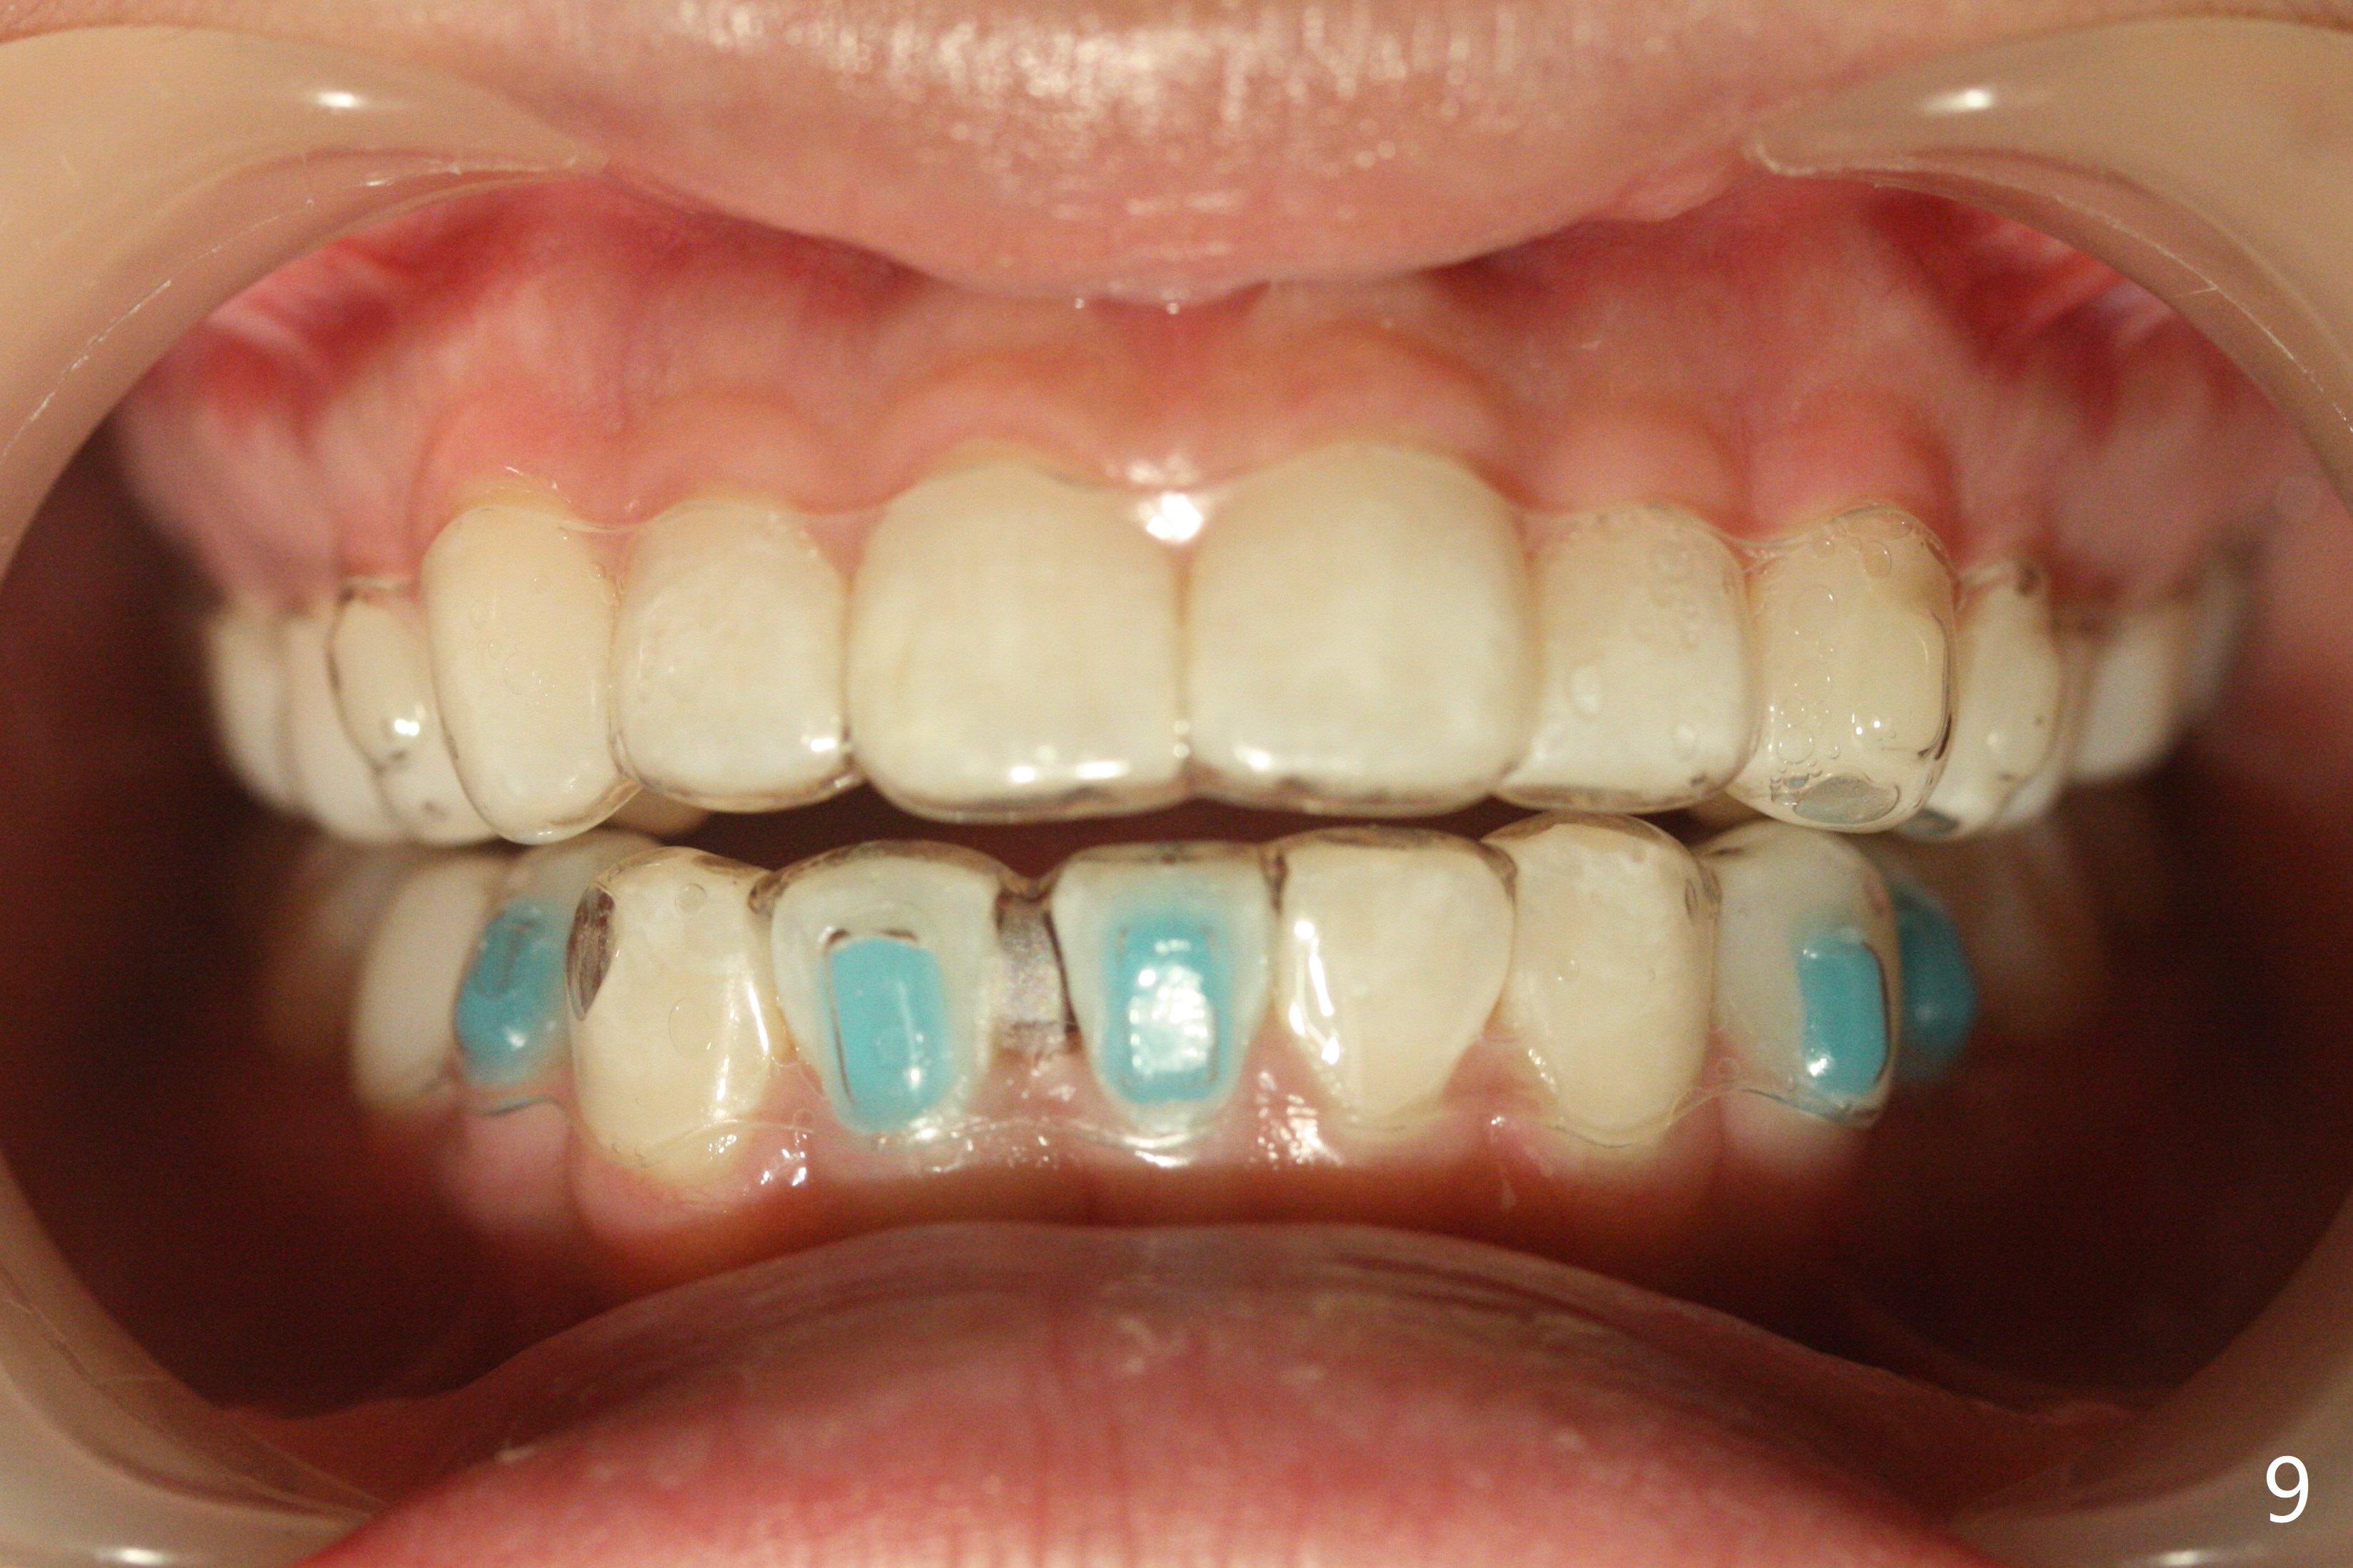

13岁女孩面型正常,先天性缺失右下1(图一,四,七),前牙深覆盖(图二),邻牙扭转(图三),治疗计划使用隐形矫正器,上牙片切,内收,关闭下切牙间隙(图八)。片切前发现上切牙邻面龋(图五,六),最大一个已经修补(右上2),不知其余小的龋坏能否片切,涂氟保守处理?不过她有龋坏易感性,以前乳牙龋坏。邻面片切后,上,下颌分别用无色和蓝色树脂做attachments(图九)。不明白的是Reciprocating saw远不如wheel利索。